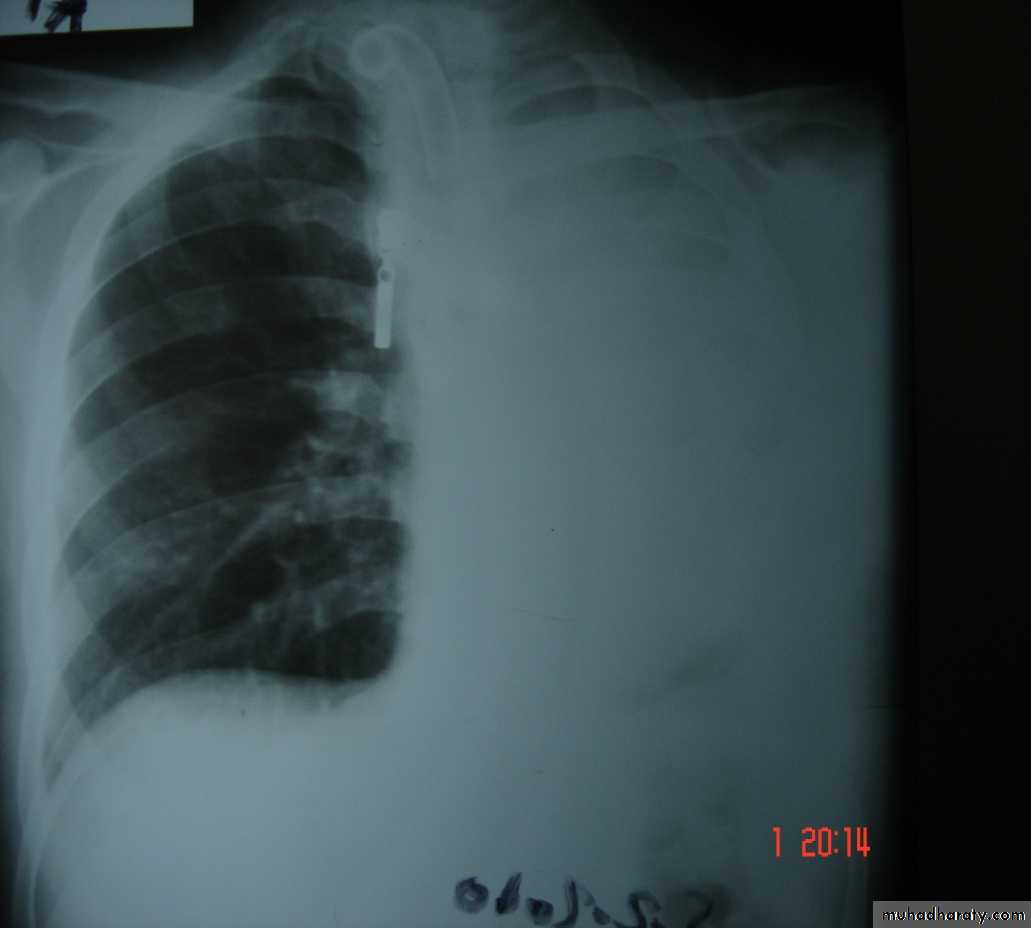

Is the accumulation of air inside the pleural cavity , occurring without any known etiology .More in males ,more on the right side .It can be bilateral

• 3-Pleurl injuries Can lead toA-Pneumothorax which can be partial or complete closed or open sucking or tension pnemothorax . B-Haemothorax may be mild or severe and may be with pneumothorax

Pneumothorax